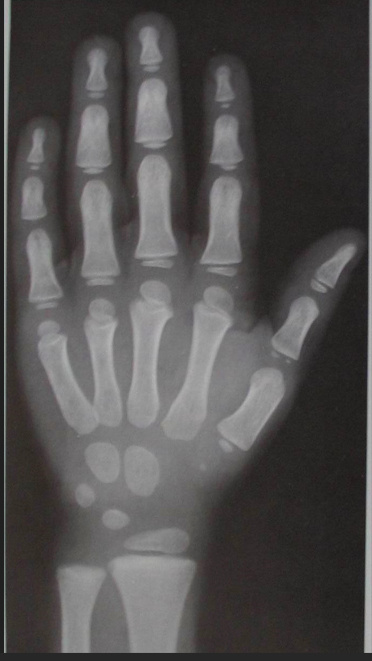

Для определения костного возраста выполняют рентгенографию кистей рук с лучезапястными суставами. Далее проводят оценку костного возраста согласно одной из систем (Greulich and Pyle, The Tanner–Whitehouse Method и другие).

Пример определения костного возраста по методике Greulich and Pyle.

Мальчик, костный возраст 4 года.